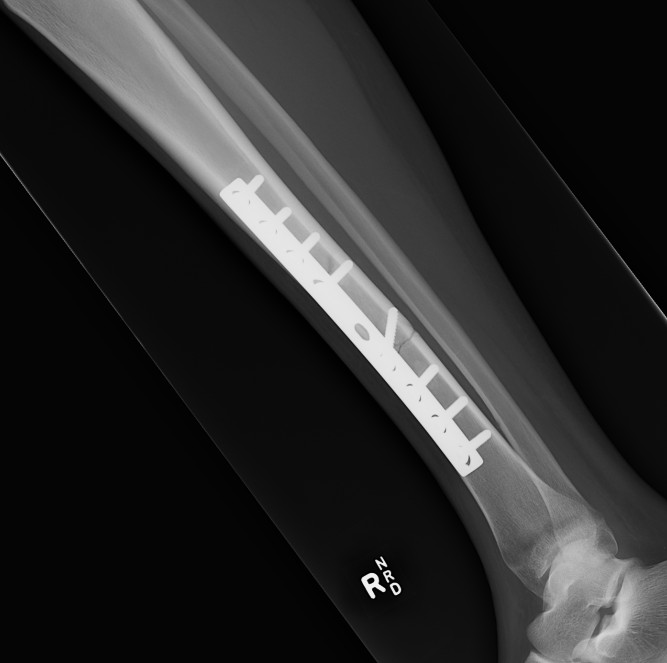

2. Plate fixation

Tibial Midshaft PlateTibial Midshaft Plate Lateral

Risk

- poor skin / blood supply / muscle cover

- excessive soft tissue stripping

Technique

- minimally invasive

- indirect reduction techniques

Results

He et al. Clinics 2014

- meta-analysis of 11 studies

- MIPO plate v IMN

- faster union rates with plate

- no increased infection or reoperation

https://www.ncbi.nlm.nih.gov/pmc/articles/PMC3971355/pdf/cln-69-04-234.pdf